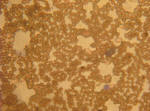

Introdução Este trabalho foi realizado no âmbito da disciplina de biologia com o objetivo de observar as preparações definitivas de sangue humano e conhecer a sua constituição bem como criar e observar a nossa própria preparação com sangue humano. O sangue é uma mistura de aspecto líquido e coloração vermelha, bombeada pelo coração, que circula dentro do sistema cardiovascular de todos os seres com um sistema circulatório fechado, exerce uma importante função vital, que consiste em transportar os nutrientes e o oxigénio para todas as células do corpo. O sangue apresenta constituintes importantes como as hemácias, que transportam oxigénio, as plaquetas que também apresentam uma importante ação nos mecanismos de coagulação do sangue e ainda os leucócitos que são maiores que as hemácias mas em menor numero e que desempenham a função de defender o organismo contra os agentes patogénico, conferindo a imunidade ao sistema. Os leucócitos apresentam-se numa grande variedade de formas, tamanhos, número, e funções específicas, exemplos destes são os linfócitos, monócitos, neutrófilos, eosinófilos e basófilos. Linfócitos Os linfócitos pequenos podem ser linfócitos T ou linfócitos B. Estes são responsáveis pela defesa e inativação dos agentes patogénicos. Monócitos São leucócitos agranulares, é a maior célula encontrada na corrente sanguínea, sendo produzida na medula óssea. Os monócitos quando se deslocam para os tecidos, recebem o nome de Macrófagos. Estes macrófagos são responsáveis pela proteção dos tecidos. Neutrófilos Possui no seu interior granulações finas e delicadas, que não possuem afinidade com os corantes hematológicos. Essas células são responsáveis pela fagocitose de pequenos microrganismos. Eosinófilos São leucócitos com um diâmetro maior do que os neutrófilos, as suas granulações são cor de laranja e seu núcleo é bilóbular. Circulam no sangue por 8 horas, seguem para os pulmões, pele e trato gastrointestinal, onde serão eliminados. Basófilos Possuem uma forma esférica e um núcleo irregular. Apresenta um citoplasma levemente basofílico (cor azul) e quase sempre ofuscado pelos vários grânulos grosseiros corados de roxo. Os grânulos estão dispostos irregularmente cobrindo também o núcleo. Apresentam dois lóbulos e raramente três ou mais. Fundamentação teórica Para a realização desta atividade laboratorial foram necessários conhecimentos sobre o sistema imunitário bem como dos diferentes tipos de leucócitos. Os seres vivos possuem mecanismos internos de defesa, que constituem o sistema imunitário, protegendo-os de doenças causadas por agentes patogénicos, conferindo imunidade. O sistema imunitário é um conjunto de órgãos, tecidos e células capaz de reconhecer os elementos próprios (toxinas por ele produzidas) e estranhos ao organismo (agentes patogénicos) e de desenvolver mecanismos que o protegem permitindo assim o seu bom funcionamento. As respostas imunitárias podem constituir uma defesa não específica, uma vez que promovem uma proteção geral contra os agentes patogénicos destruindo a maioria deles, ou uma defesa específica, que combate especificamente cada agente patogénico, é direcionada para um tipo particular de substância ou agente patogénico que tenha conseguido entrar no organismo. As defesas não específicas protegem o organismo de grande parte dos agentes patogénicos e incluem as barreiras superficiais, as barreiras químicas e celulares, a fagocitose, a resposta inflamatória e as proteínas com ação antimicrobiana. As barreiras superficiais, químicas e celulares constituem a primeira linha de defesa do organismo: a pele impossibilita a entrada dos agentes patogénicos quando intacta, o muco produzido pelas mucosas do sistema visual, respiratório, digestivo, excretor e reprodutor, as lágrimas e a saliva que funcionam também como barreira á entrada dos invasores, entre outros. A fagocitose é usada quando os agentes patogénicos conseguem ultrapassar as barreiras superficiais, químicas e celulares, consiste na ingestão e digestão dos agentes patogénicos. As células promotoras deste mecanismo são os fagócitos, que correspondem a leucócitos com capacidade de realizar a fagocitose. Quando a integridade dos tecidos é afetada e os agentes patogénicos entram no organismo, este desenvolve uma reação inflamatória os vasos sanguíneos dilatam aumentando o fluxo sanguíneo o que proporciona uma maior quantidade de leucócitos (nomeadamente fagócitos) na região afetada, para que estes atravessem os capilares por diapedese e ajudem no combate aos agentes patogénicos. As proteínas com ação antimicrobiana ativam-se promovendo uma resposta sequencial e assim podem aderir às membranas dos agentes patogénicos, ativar a resposta inflamatória atraindo os fagócitos, auxiliar os fagócitos na destruição dos agentes patogénicos e também, em colaboração com os anticorpos, promover a lise das células invasoras. Nesta experiência utilizamos o corante Wright, que consiste numa mistura de corantes, um corante básico (azul de metileno) e um corante ácido (eosinato de azul), permitindo a coloração simultânea do citoplasma e do núcleo das células. Enquanto o corante básico confere cor azul-violeta aos ácidos nucleicos, nucleoproteínas, grânulos basófilos e aos grânulos dos neutrófilos, a eosina confere cor vermelha alaranjada à hemoglobina e aos grânulos dos eosinófilos. Nesta experiência utilizamos também uma solução tampão. As soluções tampão reduzem a variação dos valores de pH, mantendo-o aproximadamente constante, mesmo com adição de pequenas quantidades de ácidos ou bases. Assim, são usadas sempre que se necessita de um meio com pH aproximadamente constante, podem ser formadas por um ácido fraco e um sal formado pela reação desse ácido com uma base forte, ou, então, por uma base fraca e um sal formado pela reação dessa base com um ácido forte. O pH do sangue é de aproximadamente 7,4 e a solução tampão mais utilizada é um equilíbrio entre o ácido carbónico e o seu ião associado, o bicarbonato. Esta solução evita variações de 0.3 unidades de pH, por isso utilizamos este tipo de soluções para podermos observar os leucócitos no sangue. Protocolo experimental Material Biológico . 1 gota de sangue Material de laboratório . Álcool 70° . Água destilada . Água tamponada (pH 6,8) . Algodão hidrófilo . Papel de filtro . Lanceta descartável . Microscópio ótico composto . Lâminas de bordo esmerilado . Tampa da caixa de Petri Corantes Corante de Wright Procedimento . Desinfetou-se a polpa de um dedo indicador. . Com a lanceta descartável picou-se a polpa do dedo desinfetado. . Deixou-se cair uma gota de sangue sobre a extremidade da lâmina. . Realizou-se um esfregaço sanguíneo procedendo do seguinte modo: . Assentou-se a lâmina de bordo esmerilado, com um inclinação de 45º, sobre a que contem a gota de sangue; . Deixou-se o sangue estender-se, por capilaridade, ao longo da linha de encontro das duas lâminas; . Fez-se deslizar a lâmina, exercendo uma ligeira pressão sobre a lâmina horizontal, arrastando assim a gota de sangue para que possa estender em camada uniforme; . Executou-se esta operação com um movimento rápido até estender toda a gota;  Agitou-se imediatamente a lâmina, com movimentos rápidos, para secar o esfregaço. Colocou-se 3 gotas de corante de Wright no esfregaço e deixou-se atuar durante 3 minutos. Adicionou-se igual quantidade de água tamponada e deixou-se atuar por 10 minutos. Escorreu-se o corante e lavou-se com água destilada. De seguida, secou-se suavemente a lâmina com papel de filtro. Por fim, registou-se e esquematizou-se as observações. Resultados Através do trabalho prático realizado pôde-se observar com clareza os diferentes tipos de leucócitos.  Fig.2 – Fotografia da preparação definitiva de sangue humano.  Fig.3 – Observação ao M.O.C da preparação definitiva de sangue humano.  Fig.4 – Fotografia de um neutrófilo.  Fig.5 – Observação ao M.O.C de um neutrófilo.  Fig.6 – Fotografia de um basófilo.  Fig.7 – Observação ao M.O.C de um basófilo.  Fig.8 – Fotografia de um linfócito.  Fig.9 – Observação ao M.O.C de um linfócito. Discussão A fagocitose é um mecanismo de defesa não específica contra agentes patogénicos que ultrapassam as barreiras superficiais de defesa. Este processo ocorre com o auxílio dos fagócitos. Os fagócitos circulam na corrente sanguínea e podem atravessar os capilares sanguíneos até aos tecidos envolventes, através de um procedimento designado por diapedese, que implica a capacidade de os leucócitos mudarem de forma, sendo importante possuírem essa capacidade para conseguirem deslocar-se até aos locais onde se encontraram os agentes patogénicos. Já no local onde se encontram os agentes patogénicos, os fagócitos reconhecem as glicoproteínas presentes nas membranas das células invasoras, aderem à sua superficie e fagocitam-os com o auxílio de enzimas proteolíticas presentes em lisossomas, que se fundem com as vesículas de endocitose. Quando um indivíduo tem uma infecção interna ou ainda em estágio inicial o número de leucócitos presentes no sangue é superior ao de um indivíduo saudável. Assim, uma das formas de detetar infecções internas ou estágios iniciais de infecção é realizar um leucograma, que quantifica os leucócitos presentes numa amostra de sangue. Para podermos adquirir informações sobre doenças que um indivíduo possa ter ou ainda sobre o estado dos orgãos, realizamos análises sanguínea pois destas podemos fazer uma rica e rápida avaliação em estados normais ou de emergência, contando-se ainda com a vantagem de que a colheita de sangue é uma técnica considerada não invasiva. É por isso importante que realizemos analises sanguineas periodicamente, para sabermos o nosso estado de saúde e podermos resolver a tempo algum problema de saúde caso este seja detectado. As analises sanguineas refletem o estado de saúde em que o paciente se encontra no momento da colheita, porém para uma boa avaliação, o clínico responsável fará uma comparação com os dados obtidos e os valores de referência. Na amostra de sangue observada nesta experiência foi possível observar e identificar 3 tipos de leucócitos: um neutrófilo, um linfócito e um basófilo. Na realização desta experiência observámos também 30 hemácias num oitavo da circunferência de observação, o que indica que numa observação de sangue humano com ampliação de 150x se encontram aproximadamente 240 hemácias presentes.  Fig.10 – Origem dos diferentes tipos de células sanguíneas, com destaque para os diferentes tipos de leucócitos. Conclusão Nesta atividade experimental, a principal dificuldade foi a de visualizar e distinguir os leucócitos pois o número de hemácias é muito superior ao dos leucócitos o que dificulta a sua visualização pois encontram-se mais dispersos que as hemácias. Face à interpretação dos resultados obtidos, esta atividade laboratorial permitiu-nos ficar a perceber quais e como se processam os vários mecanismos de defesa constituintes do sistema imunitário do nosso organismo e a saber distinguir visualmente cada um dos vários leucócitos que circulam na corrente sanguínea alem das suas características e papeis desempenhados. __________________________________ Outros Trabalhos Relacionados | Ainda não existem outros trabalhos relacionados | |